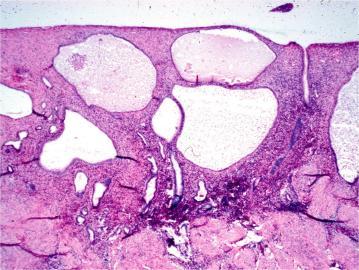

Benign prostatic hyperplasia - stromal hyperplasia

Hyperplasia of the stroma happens first